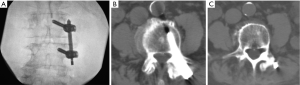

A retrospective review of every patient treated with this protocol was performed after approval of the local Institutional Review Board, and informed consent was obtained from each subject. Adult late middle aged to elderly patients with neuroimaging characteristics and a clinical exam consistent with neurogenic claudication due to focal spinal canal stenosis or discrete foraminal stenosis, combined with significant facet arthropathy and/or coexistent scoliosis were offered the combined procedure. All cases were performed in a biplanar neuroangiographic suite. After administration of a prophylactic antibiotic (1 gram either cefazolin or vancomycin), the patient was positioned prone and mildly sedated with intravenous midazolam and morphine sulfate. Local anesthesia in the lumbar skin, muscles and periosteum was achieved with a combination of 1% lidocaine and 0.5% bupivicaine. The pathologic target level was decompressed using a previously described percutaneous method of remodeling and resecting the ligamentum flavum and lamina (mild technique; Vertos Medical, Aliso Viejo, CA, USA) (4-6). In the mild technique, a 6 mm access cannula is percutaneously inserted via a 10 mm slit incision and using fluoroscopic control into the interlaminar region (Figure 1). One slit incision is required for each side of a target level. A set of single-use tools designed for working within the access cannula is then used to resect hypertrophic ligamentum flavum (tissue sculptor) and laminar/medial facet bone (bone sculptor, akin to a Kerrison rongeur). This portion of the procedure is performed under epidurographic control so as to clearly delineate the dural-epidural boundary and diminish the risk of unintentional durotomy. Bone fragments that were harvested from the lamina and medial facet involved with the stenotic segment during the decompression were saved for use in the fusion construct. Once the decompression had been completed, unilateral pedicle screw fixation was then achieved using commercially available percutaneous pedicle screw fixation techniques (Stryker, Allendale, NJ, USA; Biomet Spine, Parsippany, NJ, USA; Figure 2). If necessary, reduction of malalignment or scoliosis was gently attempted. Bone adjacent to the instrumentation on the facet and laminar surfaces was decorticated with a curette, and then the fusion construct was laid down lateral to the instrumentation. The fusion construct was composed of the laminar bone fragments, which were embedded into a bone-marrow aspirate-soaked allograft-derived demineralized bone matrix sponge (Osteosponge, Bacterin International Holdings, Belgrade, MT, USA) and demineralized bone matrix (Osteoputty, Bacterin International Holdings). The sponge, which acts as a malleable carrier as well as osteobiologic, is then inserted digitally onto the facet region through the pedicle screw access path, taking care to place the autograft bone fragments between the facet surface and the sponge. Skin incisions were closed in a single layer with 3-0 polyglycolic acid suture (Vicryl Rapide, Ethicon, Cincinnati, OH, USA). Patients were allowed to recover for 2–4 hours, then ambulated and discharged to home within 23 hours.